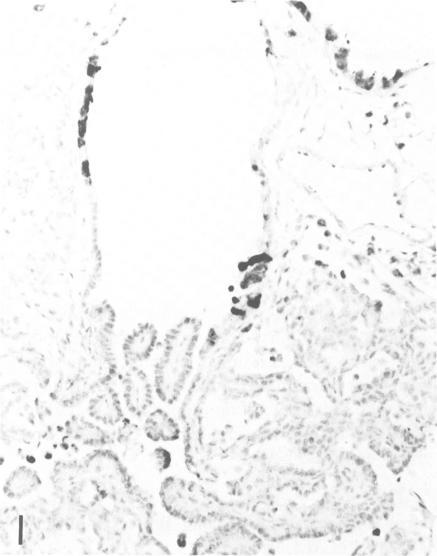

The localization of surfactant apoprotein (SAP) and the Clara cell antigen(s) (CCA) was studied in naturally occurring and experimentally induced pulmonary hyperplasias and neoplasms by avidin-biotin peroxidase complex (ABC) immunocytochemistry. Lungs of B6C3F1 and A strain mice with naturally occurring lesions, B6C3F1 mice given injections of N-nitrosodiethylamine (DEN), BALB/c nu/nu or nu/+ mice exposed transplacentally on Day 16 of gestation to ethylnitrosourea (ENU), or BALB/c nu/+ mice exposed to ENU at 8-12 weeks of age were preserved in formalin or Bouin's fixative. After ABC immunocytochemistry, SAP was found in the cytoplasm of normal alveolar Type II cells; in the majority of cells in focal alveolar and solid hyperplasias originating in peribronchiolar or peripheral locations; and in solid, tubular, papillary, and mixed adenomas and carcinomas. The larger mixed-pattern neoplasms and small or large tubular neoplasms usually had the least number of cells with SAP. The majority of large papillary adenomas and carcinomas in BALB/c mice exposed to ENU and in untreated A strain mice contained SAP in the nuclei of many neoplastic cells but only in the cytoplasm of a few neoplastic cells. CCA was found in normal Clara cells of bronchi and bronchioles but not in any hyperplastic or neoplastic lesion of any mouse studied. This study provided immunocytochemical evidence that the vast majority of naturally occurring and experimentally induced pulmonary neoplasms of mice are alveolar Type II cell adenomas and carcinomas.

采用抗生物素蛋白-生物素过氧化物酶复合物(ABC)免疫细胞化学方法,研究了表面活性物质载脂蛋白(SAP)和克拉拉细胞抗原(CCA)在自然发生和实验诱导的肺增生及肿瘤中的定位。对患有自然病变的B6C3F1和A品系小鼠、注射N-亚硝基二乙胺(DEN)的B6C3F1小鼠、在妊娠第16天经胎盘暴露于乙基亚硝基脲(ENU)的BALB/c裸鼠或裸+/+小鼠,或在8-12周龄时暴露于ENU的BALB/c裸+/+小鼠的肺组织,用福尔马林或布因氏固定液保存。经过ABC免疫细胞化学检测,发现SAP存在于正常肺泡II型细胞的细胞质中;存在于起源于细支气管周围或周边部位的局灶性肺泡增生和实性增生的大多数细胞中;也存在于实性、管状、乳头状和混合性腺瘤及癌中。较大的混合型肿瘤和小或大的管状肿瘤中通常含SAP的细胞数量最少。在暴露于ENU的BALB/c小鼠和未经处理的A品系小鼠中的大多数大乳头状腺瘤和癌,在许多肿瘤细胞的细胞核中含有SAP,但仅在少数肿瘤细胞的细胞质中含有。在支气管和细支气管的正常克拉拉细胞中发现了CCA,但在所研究的任何小鼠的增生性或肿瘤性病变中均未发现。本研究提供了免疫细胞化学证据,表明小鼠中绝大多数自然发生和实验诱导的肺肿瘤是肺泡II型细胞腺瘤和癌。